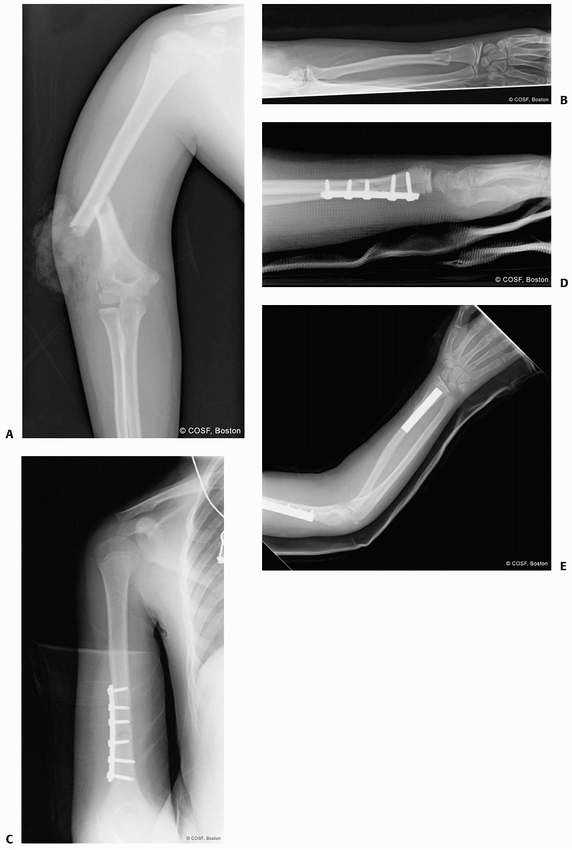

![]() |

FIGURE 9-2 Ossification of the distal radius. A. Preossification distal radius with transverse ossification in a 15-month-old boy. B. The triangular secondary ossification center of the distal radius in a 2-year-old girl. C. The initial ossification center of the styloid in this 7-year-old girl progresses radially (arrow). D. Extension of the ulnar ossification center into the styloid process of an 11-year-old. E. The styloid is fully ossified and the epiphyses have capped their relative metaphyses in this 13-year-old boy.